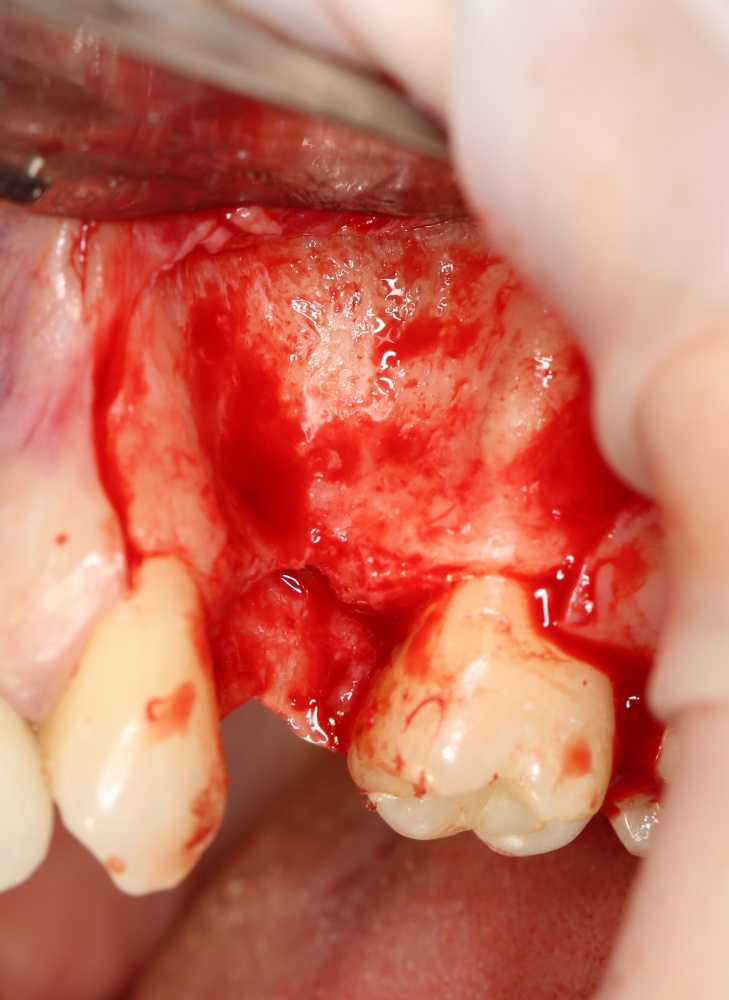

Простой. Надежный. Дешевый. Способ остеопластики.